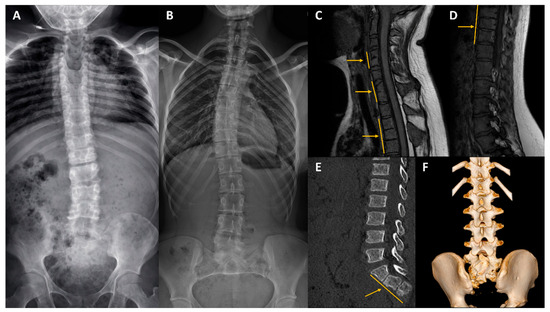

Deciphering the Genetic Basis of Congenital Vertebral Malformations Through a Stepwise Diagnostic Approach

by Anna Szoszkiewicz, Anna Sowińska-Seidler, Aleksandra Wnuk-Kłosińska, Ewelina Bukowska-Olech, Karolina Biel, Karolina Matuszewska, Marcin Biel, Magdalena Badura-Stronka, Renata Glazar, Anna Jakubiuk-Tomaszuk, Maciej Krawczyński, Krzysztof Szczałuba, Karolina Śledzińska, Marzena Wiśniewska and Aleksander Jamsheer

Int. J. Mol. Sci. 2026, 27(4), 1752; https://doi.org/10.3390/ijms27041752 - 11 Feb 2026

Congenital vertebral malformations (CVMs), affecting approximately 0.5–1 per 1000 live births, occur either in an isolated form or as part of syndromic disorders. Despite the identification of numerous causative genes for CVMs, the molecular etiology of most cases remains unknown. In this study, [...] Read more.

Congenital vertebral malformations (CVMs), affecting approximately 0.5–1 per 1000 live births, occur either in an isolated form or as part of syndromic disorders. Despite the identification of numerous causative genes for CVMs, the molecular etiology of most cases remains unknown. In this study, we applied a three-tiered diagnostic approach (chromosomal microarray analysis, followed by custom gene panel analysis, and exome/genome sequencing) in a cohort of 34 patients with CVMs. We achieved a 12% diagnostic success rate, identifying a deletion upstream of SOX9 and pathogenic or likely pathogenic variants in FLNB and KMT2D. Most pathogenic variants were detected by exome or genome sequencing, while earlier-tier analyses yielded limited results. We also identified two candidate genes, NSD2 and TBXT, that may contribute to the phenotype observed in our patients, but warrant future functional validation. Our work expands the molecular spectrum of CVMs and highlights the utility of comprehensive genomic testing for improving diagnosis and understanding of vertebral development disorders. Full article

(This article belongs to the Special Issue Genomic Research of Rare Diseases)

Show Figures

Figure 1